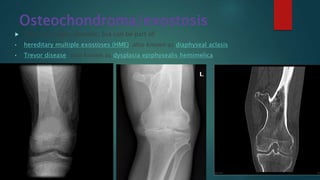

Osteochondroma/exostosis

 They are usually sporadic, but can be part of:

• hereditary multiple exostoses (HME): also known as diaphyseal aclasis

• Trevor disease: also known as dysplasia epiphysealis hemimelica